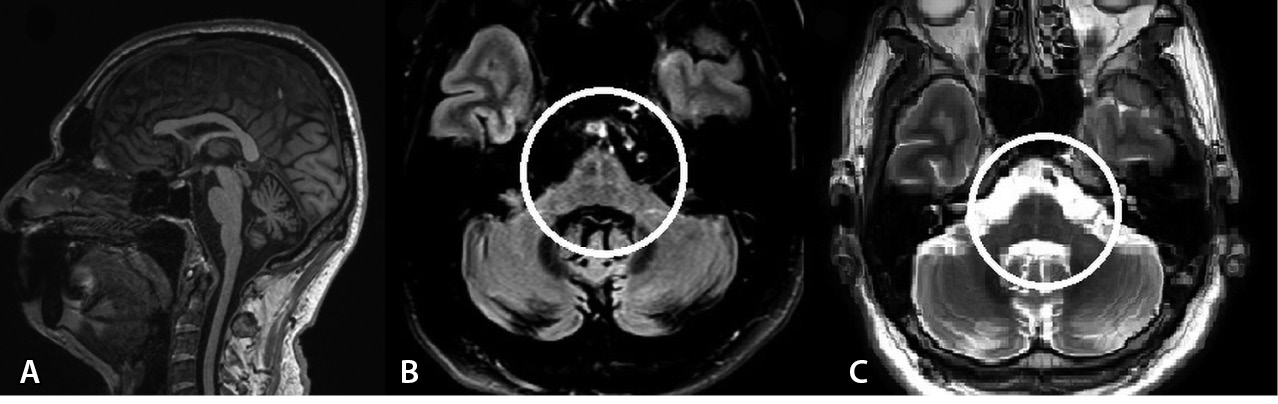

По данным УЗИ остаточной мочи ее объем составил 51 мл, по данным МРТ головного мозга в режиме T2-FLAIR выявлен линейный участок повышенного сигнала от скорлупы, гипоинтенсивный в режиме SWI, в режиме Т1 – признаки атрофии варолиева моста, мозжечка (рис. 2).

Рис. 2. Магнитно-резонансная томография головного мозга пациента А. А – Т2-FLAIR, аксиальный срез: симметричные линейные участки повышенного сигнала от скорлупы (отмечено стрелками). Б – SWI, аксиальный срез: симметрично сниженная интенсивность сигнала от скорлупы (отмечено стрелками). В – Т1-взвешенное изображение, сагиттальный срез: признаки атрофии варолиева моста, мозжечка (отмечено стрелкой)

На основании критериев диагностики МСА от 2022 г. пациенту А. был поставлен диагноз клинически достоверной МСА-П.